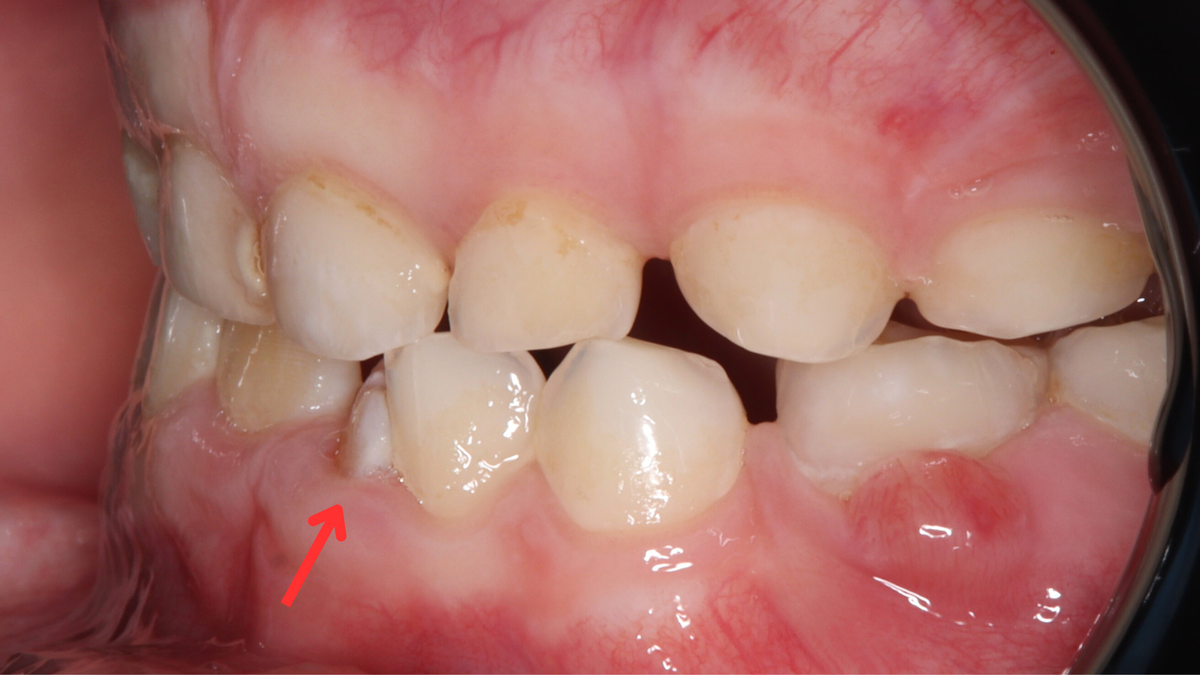

- В большинстве случаев тортоаномалия возникает у однокорневых зубов — в первую очередь у резцов и клыков верхней и нижней челюсти. Нередко аномалия встречается и у премоляров.

- Любая аномалия положения зубов может привести к негативным последствиям. Когда зубы стоят неровно — особенно если таких несколько и они повёрнуты под разными углами — между ними легко застревает пища, а качественно почистить такие участки становится крайне сложно.

В результате постоянно скапливается мягкий зубной налёт, который создаёт идеальную среду для размножения бактерий. Под налётом сначала появляются белые меловые пятна — признак деминерализации эмали. Со временем эмаль истончается, пятна увеличиваются, и на этом месте формируется кариозная полость.

Кроме того, постоянное скопление налёта и бактерий со временем может привести к развитию гингивита (воспаление дёсен), кровоточивости дёсен, раздражению слизистой оболочки полости рта.